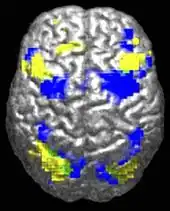

The underconnectivity theory of autism posits that autistic people tend to have fewer high-level neural connections and less global synchronization, along with an excess of low-level processes.[31] Functional connectivity studies have found both hypo- and hyperconnectivity in brains of autistic people.[32] Hypoconnectivity is commonly observed for interhemispheric (e.g. lower neuron density in corpus callosum)[33] and cortico-cortical functional connectivity.[34] Some studies have found local overconnectivity in the cerebral cortex and weak functional connections between the frontal lobe and the rest of the cortex.[35] Abnormal default mode network (task-negative) connectivity is often observed. Toggling between task-negative network activation and task-positive network activation (consisting of the dorsal attention network and salience network) may be less efficient, possibly reflecting a disturbance of self-referential thought.[36] Such patterns of low function and aberrant activation in the brain may depend on whether the brain is performing social or nonsocial tasks.[37]

Brains of autistic individuals have been observed to have abnormal connectivity and the degree of these abnormalities directly correlates with the severity of autism. Following are some observed abnormal connectivity patterns in autistic individuals:[33][18]

- Prominent abnormal connectivity in the frontal and occipital regions. In autistic individuals low connectivity in the frontal cortex was observed from infancy through adulthood. This is in contrast to long-range connectivity which is high in infancy and low in adulthood in ASD.[33] Abnormal neural organization is also observed in the Broca's area which is important for speech production.[18]